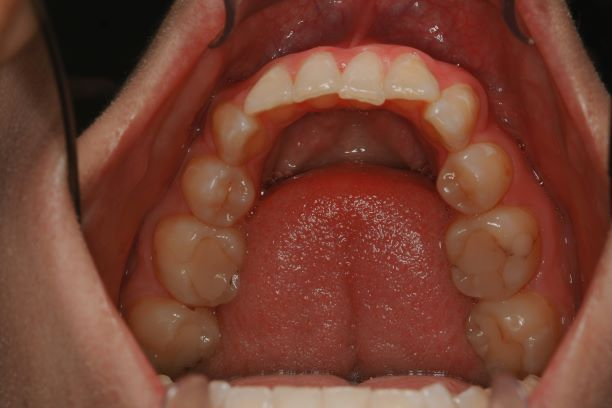

Tipped Teeth

In the above picture see how the teeth are pointing towards the tongue. This limits the amount of space for the tongue.

Do you see how the tongue fills in the space between the teeth?... this is what causes the scalloping appearance on the sides of the tongue.

When the tongue doesn't have enough space to rest, it often falls back obstructing your airway - hence why we are talking about sleep apnea.